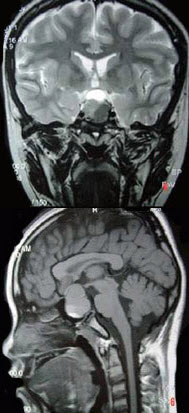

109、单项选择题

男,47岁,视物模糊数月,头痛、恶心、呕吐3天,行MRI检查如图,最可能的诊断为()

A.颅咽管瘤

B.脑膜瘤

C.垂体瘤并出血

D.蛛网膜囊肿

E.表皮样囊肿